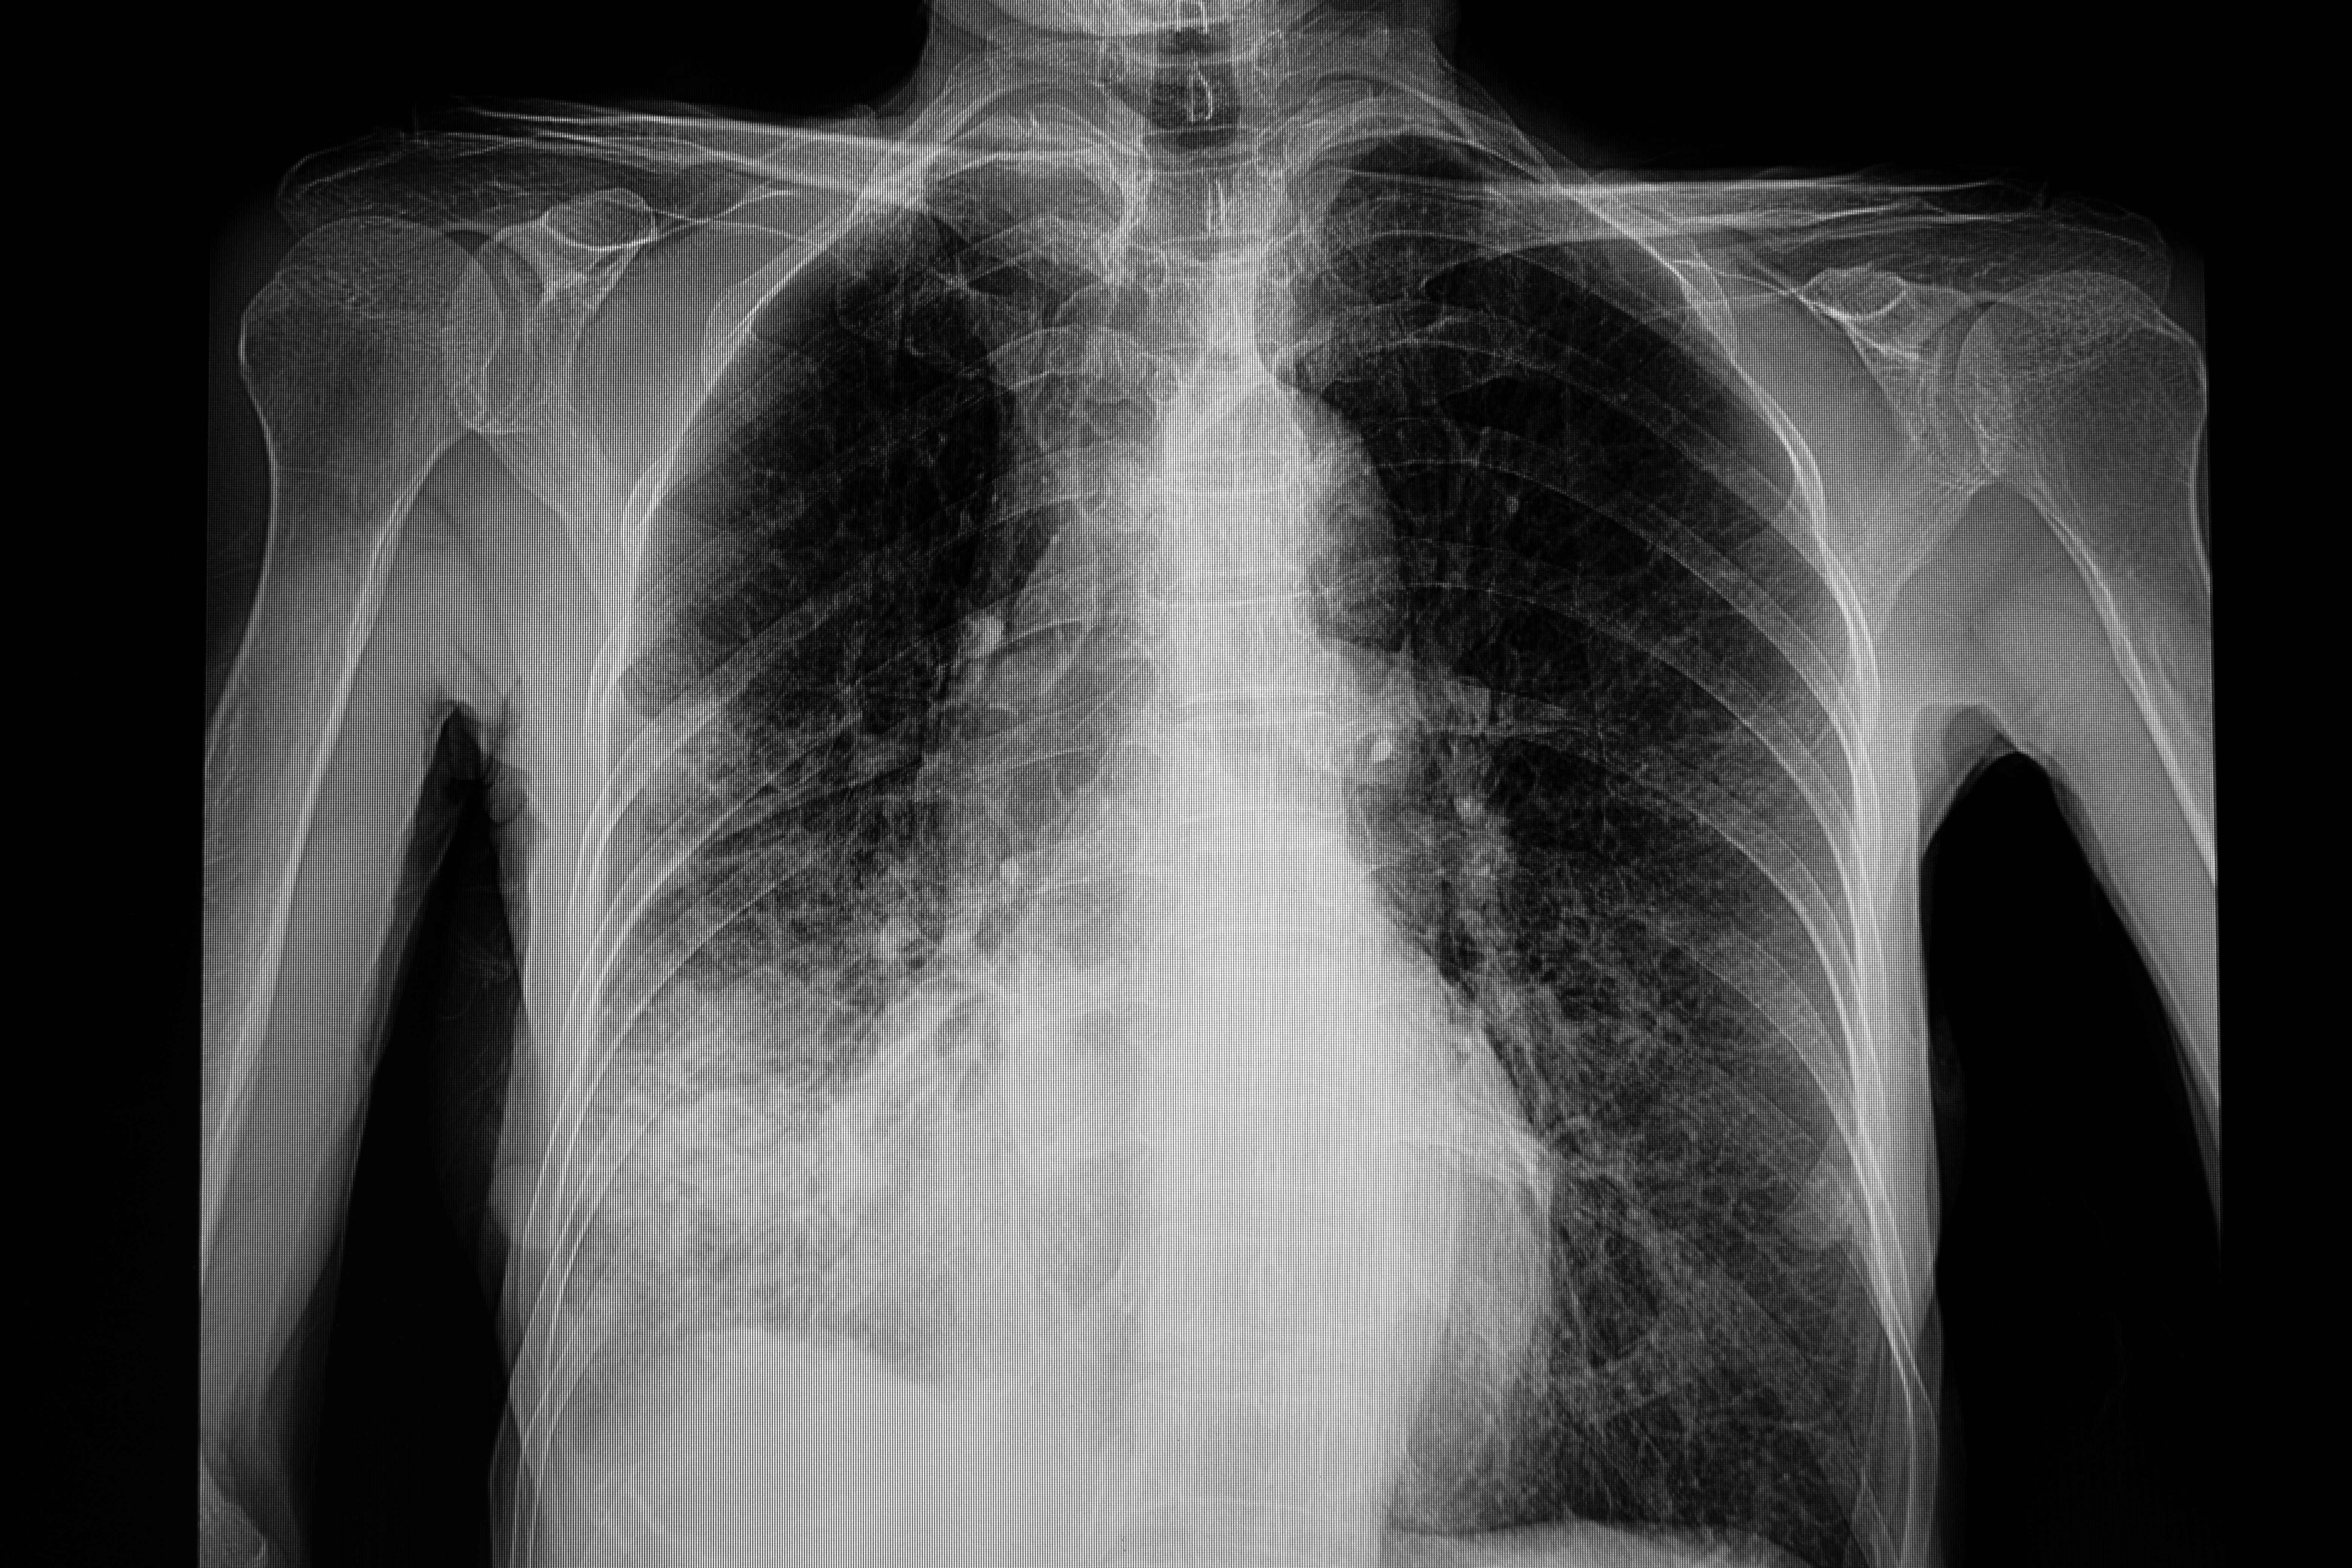

In a new national coverage determination, the Centers for Medicare and Medicaid Services (CMS) have lowered the starting thresholds for lung cancer screening from 55 to 50 years of age and from a 30-pack/year tobacco smoking history to 20 packs a year.